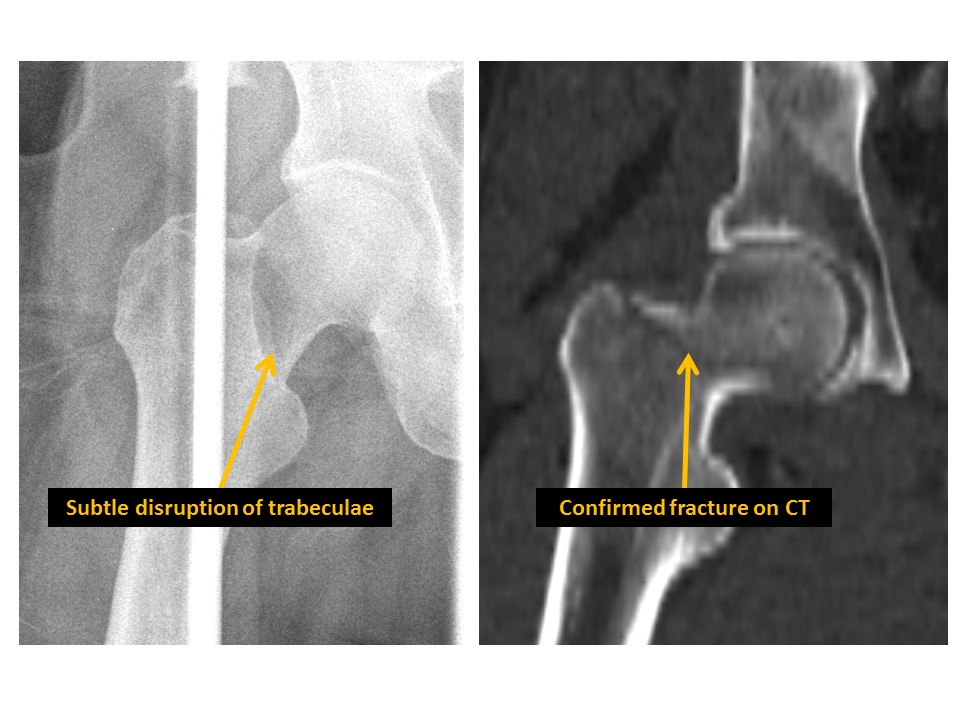

There are fractures of the femoral neck, intertrochanteric region, or subtrochanteric region. [Yes/No]

The trabecular pattern of the proximal femurs is abnormal. [Yes/No]